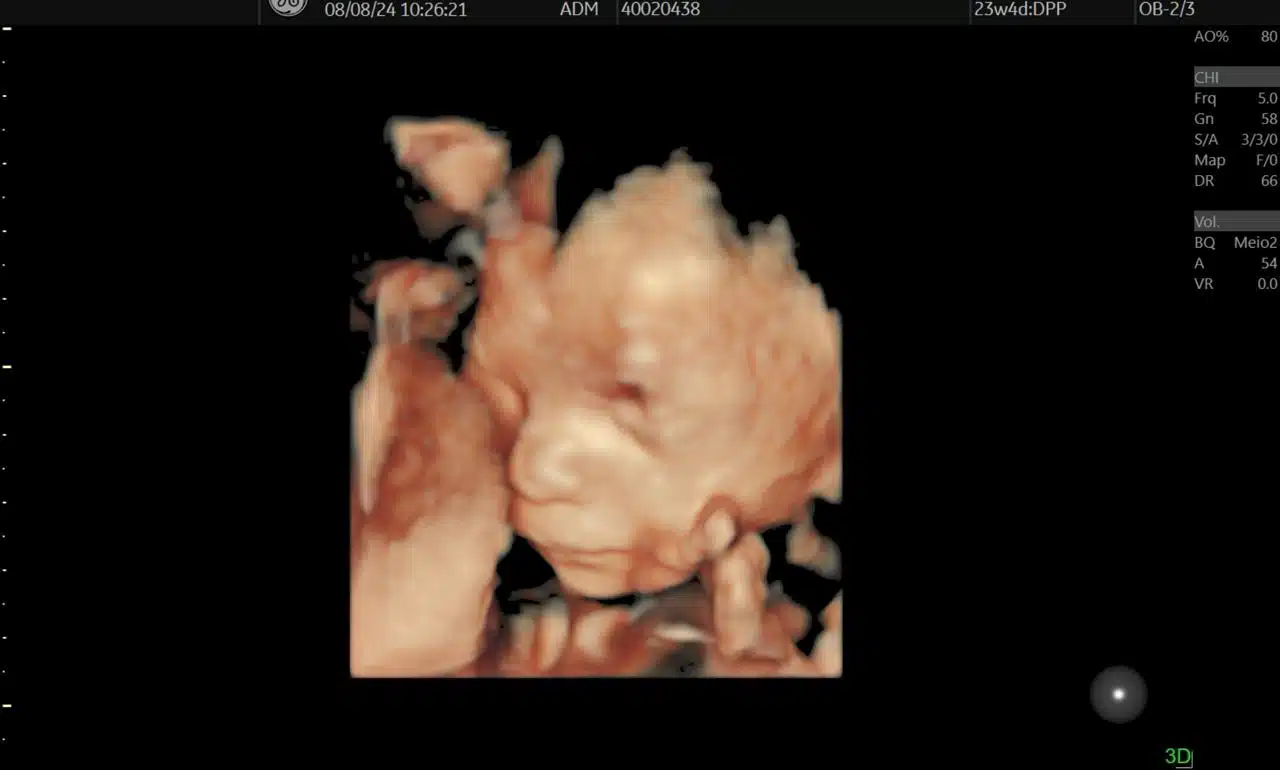

Ultrassonografia Obstétrica com e sem 3D

A ultrassonografia obstétrica é fundamental para o acompanhamento do desenvolvimento do feto. Com a tecnologia 3D, é possível visualizar detalhes incríveis do bebê, proporcionando um acompanhamento ainda mais detalhado durante a gestação.